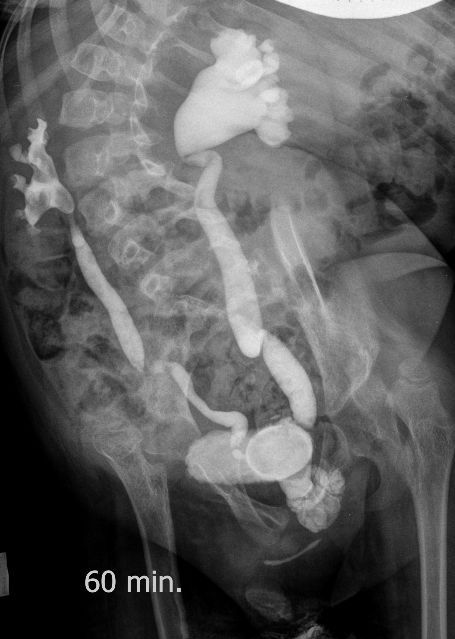

Поскольку откликов нет, добавляю экскреторные урограммы этого же пациента

Нейрогенный мочевой пузырь (?), МКБ, конкремент мочевого пузыря, двухсторонний мегауретер, конкремент правой почки.

И что законтрастировалось на экскреторных урограммах около мочевого пузыря?

DX0004.jpg

Стриктура уретры с расширением ее проксимального отдела?

Если честно, и я изначально не совсем понял, где находится конкремент (а это конечно же конкремент), локализованный на урограммах. При первичном исследовании на УЗИ его я не видел (либо он спрятался за тенью конкремента мочевого пузыря, либо я обрадовался редкой находке конкремента такого размера в мочевом пузыре - 2.5 см, и не посмотрел что ниже). Тем не менее при ретроспективном анализе архивированных сонограмм, как мне кажется, он попал в один из сканов, м.б. не совсем чётко.

И всё -же, где конкремент :?:

Возможно, в дивертикуле либо в нижней трети мочеточника..

Верификация:

Выдержка из протокола операции- "...вскрыт мочевой пузырь, обнаружен камень 4 х 3х 2.5 см, плотный, удалён. При дальнейшей ревизии мочевого пузыря обнаружен вколоченный камень в шейке мочевого пузыря и в уретре, удалён камень 2 х 1.5 х 1.5 см. При осмотре устья левого мочеточника - последний зияет, мочеточник расширен до 1 см, учитывая расширение мочеточника, проведена антирефлюксная пластика по Грегуару..."

На экскреторной урограмме - размеры собирательной системы левой почки уменьшились. Визуализирована расшиенная контрастированная проксимальная уретра.